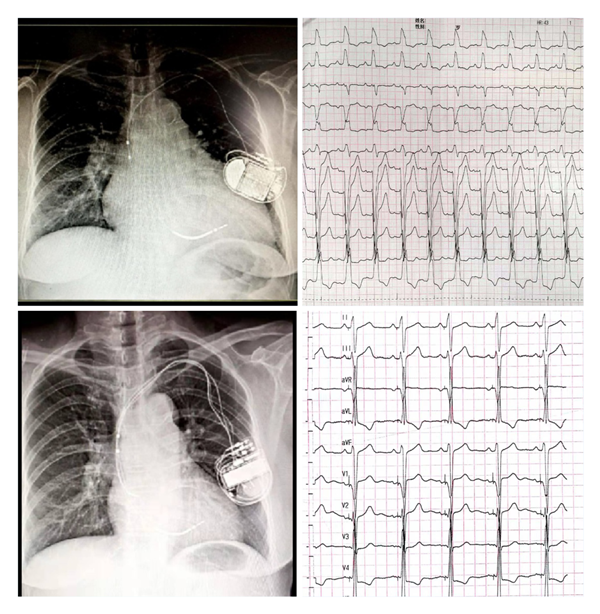

国产自拍 为国内较早开展左束支起搏(LBBP)的中心之一,自2018年1月开展福建省首例LBBP以来,至今累计例数已近200例。中心采用黄伟剑教授的标准术式,手术成功率高、并发症少,随访导线参数稳定。此前起搏团队为1例外院CRT失败转诊国产自拍 的患者实行左束支起搏治疗得到了良好的疗效,LVD从80mm 缩小至52mm,LVEF 从24%升高至60%,心脏完全恢复正常。目前厦心常规开展这一技术以造服更多的心衰患者。

(上图左上为CRTD术前,外院植入ICD2年,右上是自身完左心电图;左下为CRTD术后一年,右下为CRTD术后心电图)